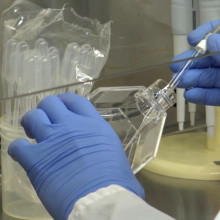

Clinical trials begin to treat COVID-19 patients with sepsis

It’s a discovery that has been more than ten years in the making: the use of a human protein to potentially treat patients with sepsis. Lawson Scientist Dr. Qingping Feng noticed that a human protein called annexin A5 showed positive results with sepsis back in 2007. Fast forward 14 years later to now, and this discovery could very well be the first ever viable treatment for sepsis patients, including severe COVID-19 patients who develop sepsis. Read more.